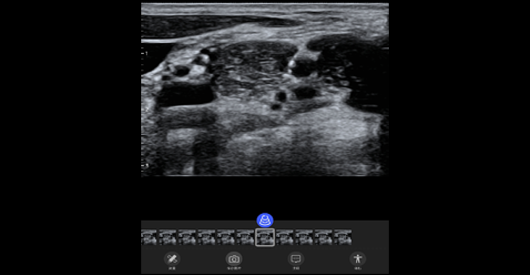

臂丛神经

探头类型:线阵探头。典型场景:血管、小器官。